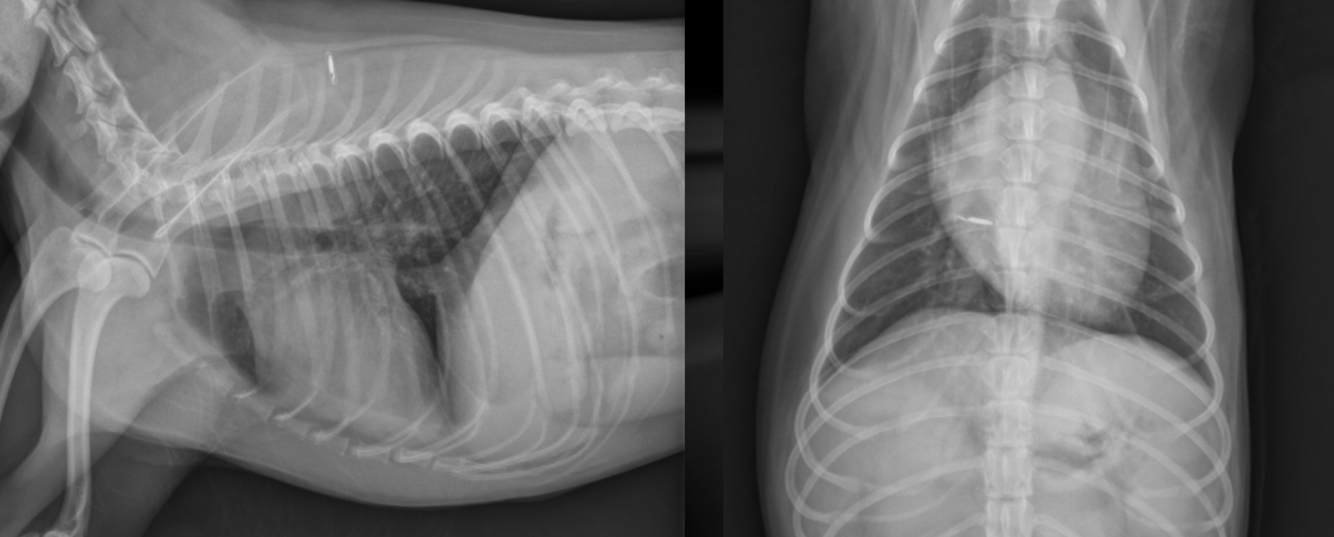

What is shown in these images?

acquired (traumatic) diaphragmatic hernia

-abnormal soft tissue content in thoracic cavity

-no diaphragm outline noted

-shifted gastric axis

-small intestine present within chest cavity and dilated